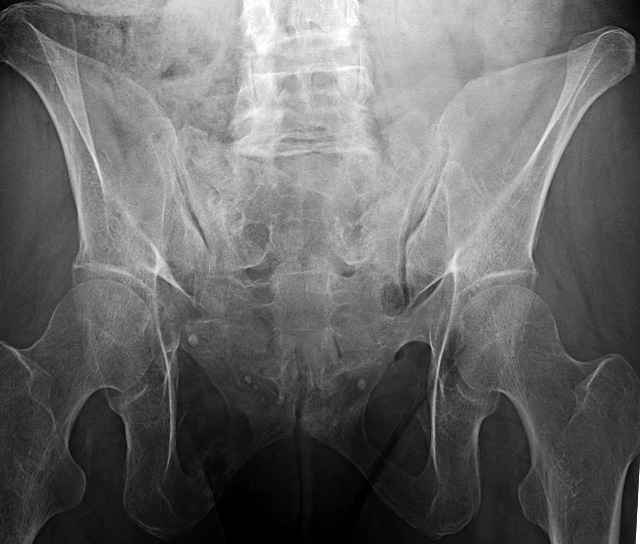

Here are a recent patient’s example slides...

54 yo Female Fell c/o Pain

Initial Films

?Instability on Exam - Limited by Pain

NonOp Initial Mgmt